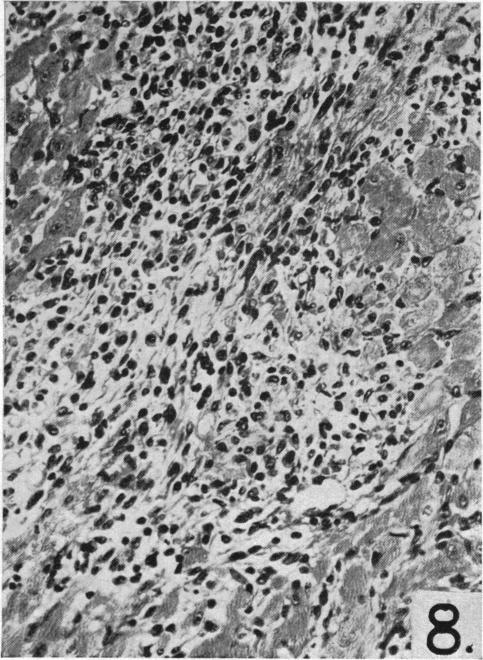

Dietary choline and the maintenance of the cardiovascular system in rats.

Br Med J. 1954 Jul 3;2(4878):1-5. doi: 10.1136/bmj.2.4878.1.